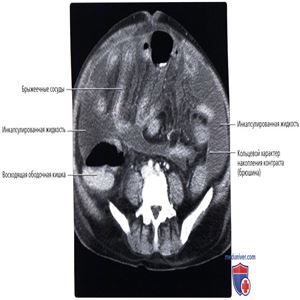

КТ с контрастированием, аксиальный срез: у этого же пациента определяются множественные инкапсулированные внутрибрюшинные скопления жидкости по всему объему полостей живота и таза, включая два крупных скопления, распространяющихся вниз по ходу боковых каналов брюшной полости. Брюшина, прилегающая к скоплениям, уплотнена и накапливает контрастное вещество. Сочетание этих признаков характерно для перитонита с формированием абсцесса.

Каждый из листков брыжейки тонкой кишки выглядит жестким с выпрямленными брыжеечными сосудами и покрыт уплотненной брюшиной, накапливающей контрастное вещество. Париетальный листок брюшины также уплотнен и накапливает контраст, что обусловливает наличие у каждого инкапсулированного скопления жидкости капсулы или ободка. Срастание воспаленных поверхностей брюшины вносит вклад в инкапсулирование жидкости.